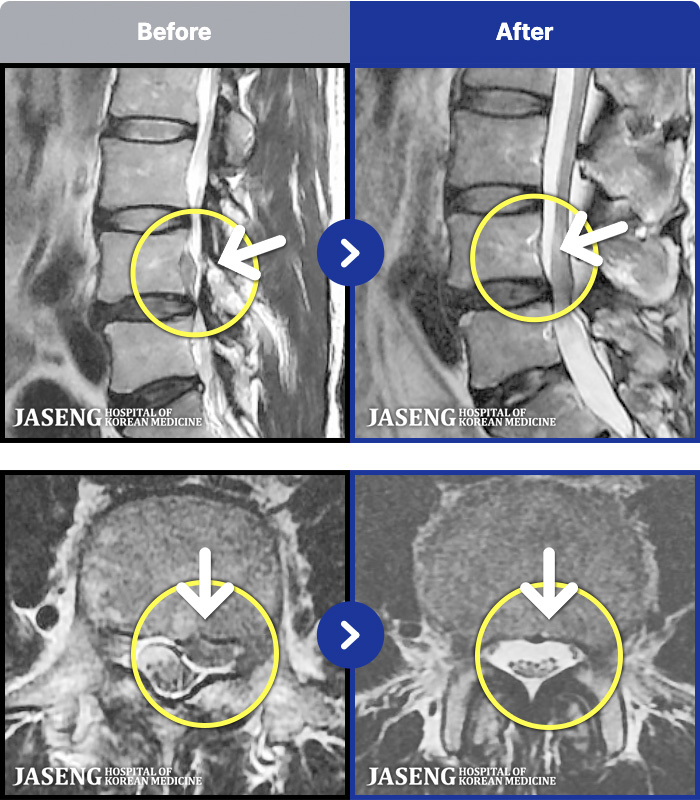

- MRI ġ

MRI ġ

1,240 MRI ũ ʸ Ȯϼ.